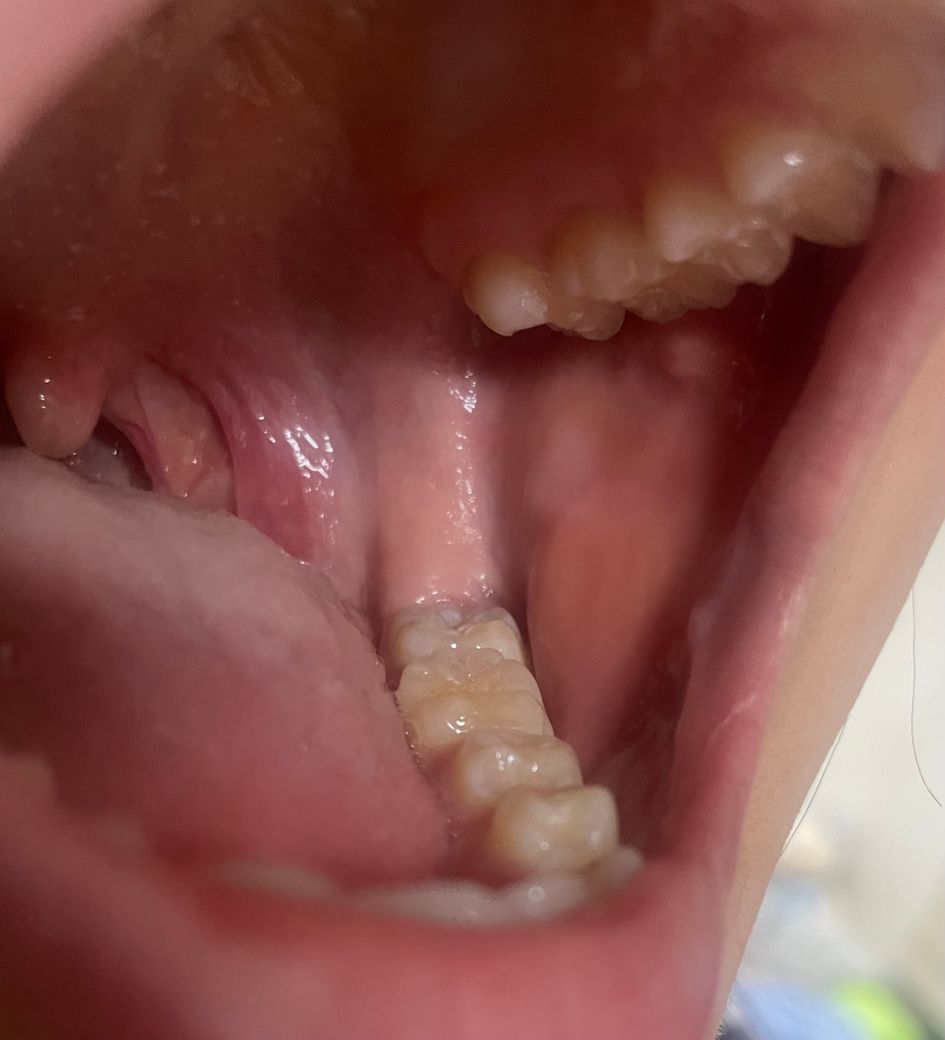

입안에 뭐가 낫는데 어느 병원 가야할까요

입안에 양쪽 뭐가 동그랗게 낫는데 아프진않아요

양쪽 똑같은 위치에 낫어요 어느병원가야

정확히 이게 뭔지 알 수 있나요? 한3일되었습니다.

• 1번 째 사진

우리 몸에 존재하는 정상적인 타액선으로 보여집니다. 다만 사진만으로는 정확한 판단이 어려우며 너무 불안하시다면 가까운 치과 방문 후 검사를 한 번 해보시길 바랍니다. 사진으로는 parotid gland일 가능성이 있어 보입니다.

대단한건 아닌거 같습니다. 볼살이 씹혀서 과증식 된거 같습니다. 걱정하지 않으셔도 될것같습니다.